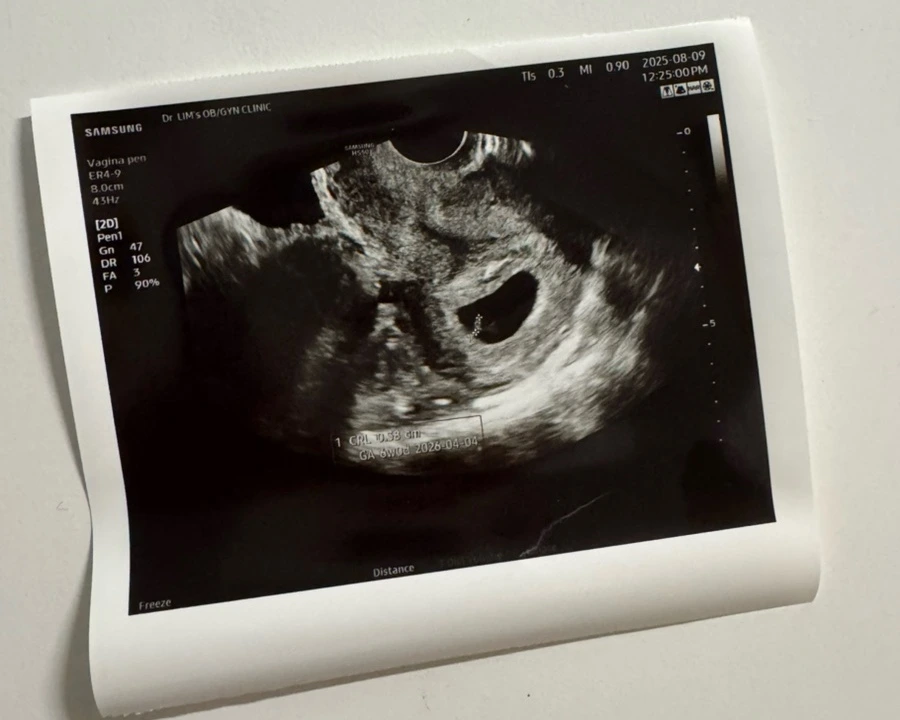

임신테스트기의 세 줄을 확인하고서(요즘은 세 줄짜리도 나온다) 기쁘면서도 걱정스러웠다. 다음날 산부인과를 찾았다. 임신 테스트기에서 양성이 떠서 왔다고 했다. 진료실로 들어가자 초음파를 볼 예정이라며, 의자에 치마를 겉어 올리고 앉으라고 했다. 영문을 모르는 내가 “오늘 뭐 보는 거예요?”하고 물으니 간호선생님은 “초음파 보러 오신 거 아니에요? 임신테스트기 양성이면 초음파 보는 거죠”하고 당연한 걸 묻냐는 듯 대답하셨다. 그리고선 바로 초음파로 아기집을 확인해 주었다. 초음파를 보는데 내 자궁 속 작은 구멍이 보였고, 그 안에서 새싹 하나가 피어오른 모양이 보였다. 아기 심장 소리까지 들려주시는데, 두 눈이 동그래졌다. 준비 없이 엄마가 된 기분이었다.